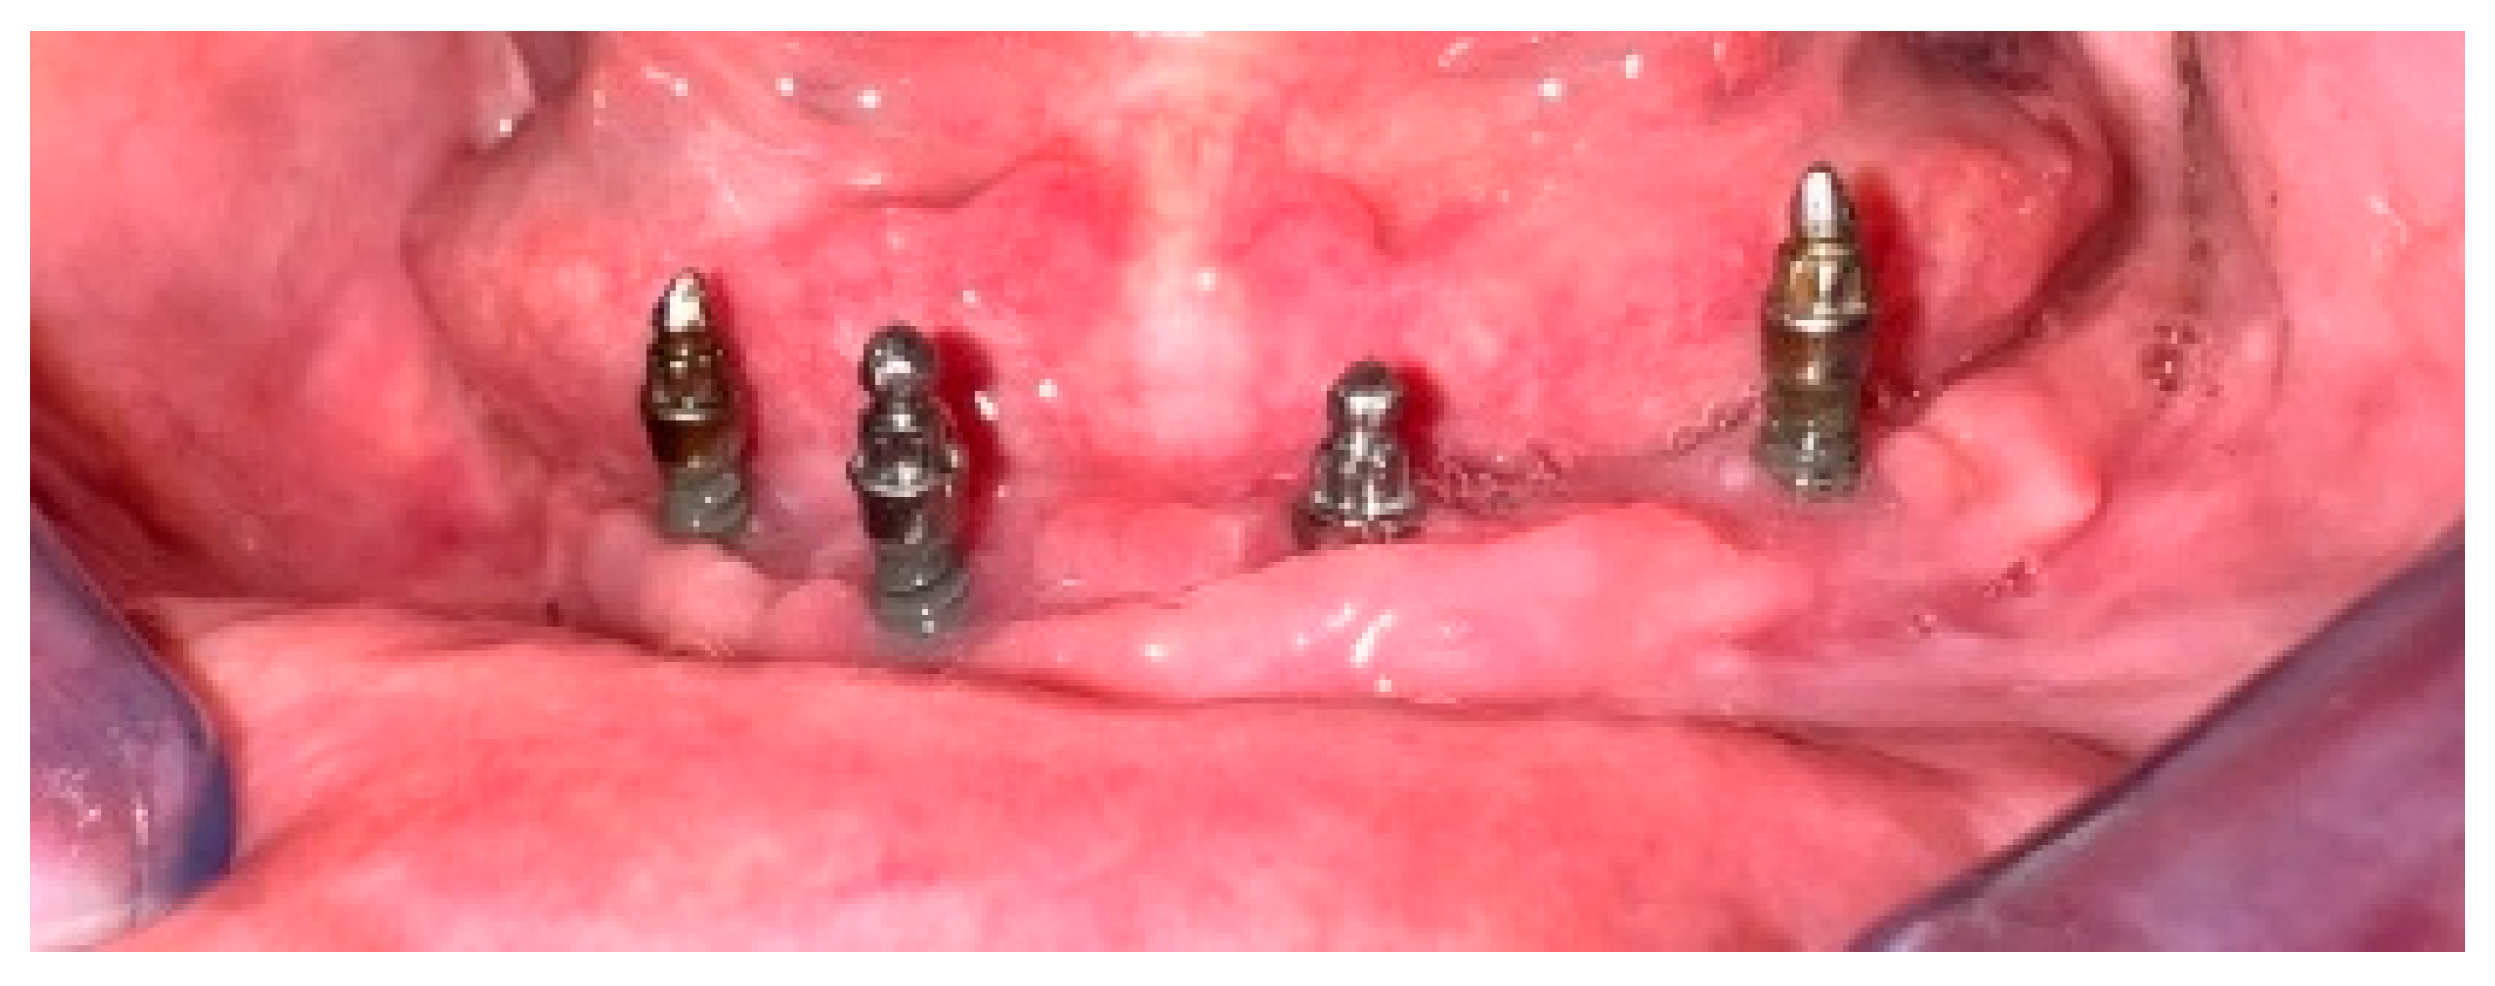

2.3. Fractures of Mandibular Overdentures and the Occurrence of Ball Abutments Wear